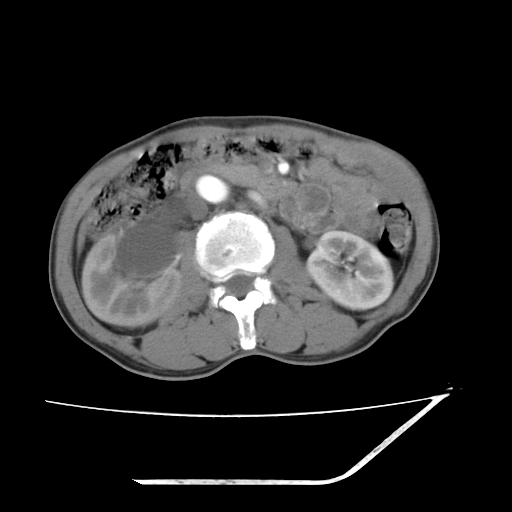

增强

考虑右肾盂癌,肾动脉受侵,右肾功能减退,右肾盂输尿管积水,管壁增厚,考虑种植转移,应该把下面扫完的

支持右侧肾盂癌伴肾静脉瘤栓形成可能性大,右肾结石.肝右叶后段低密度影,不除外转移.

考虑右侧肾盂癌。右侧输尿管扩张未扫描完。

右肾盂癌,肾动脉受侵,右肾盂输尿管积水,管壁增厚,考虑种植转移

右肾盂移行细胞癌并右输尿管中段转移.肾积水.

1.右侧肾盂癌伴肾盂积水。

2.肾脏功能减退,原因有:(1)肾动脉受侵。(2)肾静脉受侵(3)肾积水,等。本例,肾动脉显影较好,但受压明显;肾静脉无明显显示,受压或静脉癌栓,下腔静脉腔内未见明显充盈缺损。

3.右侧上段输尿管扩张,原因:(1)积水所致;(2)种植。